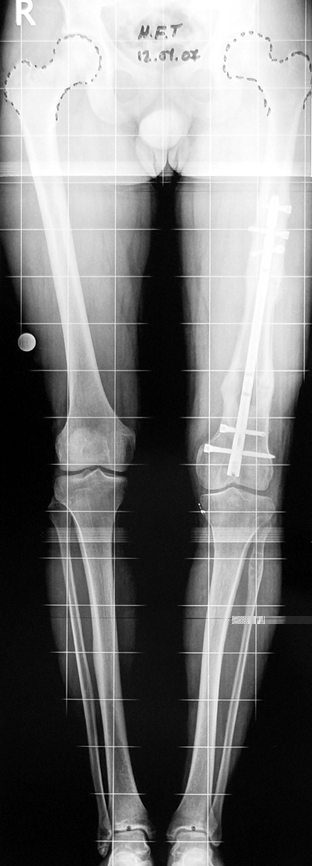

3. POSTTRAUMATIC LOWER LIMB SHORTNESS (MALUNION)

This type of shortness occurs after a fracture heals in a shortened position. Most cases are seen in adults and can be treated with one lengthening operation. Additional deformities can be corrected simultaneously. Most of these cases can be treated with lengthening over nail or just corrections and intramedullary nailing.